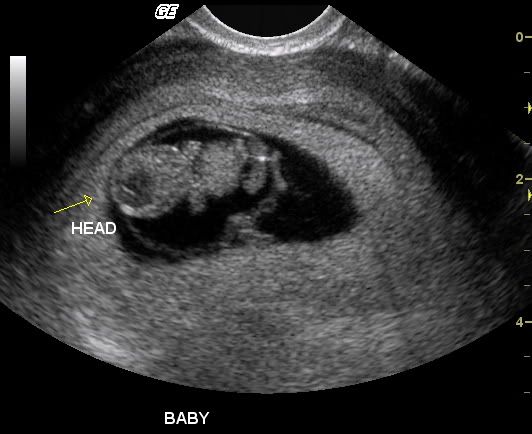

We had our appointment today, we are relieved that not only is the baby okay; but there is only one... They got us in right away but me and my son had to wait outside for awhile until they had finished. Then they copied everything to CD for us, which I really appreciate.

So heres our new baby at 9 weeks: